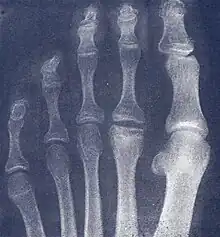

| Freiberg disease as seen on plain film | |

- Radiography: X-rays may reveal flattening, sclerosis, or fragmentation of the metatarsal head.